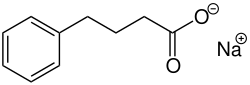

.jpg)

It has been thought that HDAC inhibitors (HDACi's) could partially reverse the low acetylation levels seen in patients with HD. Preclinical studies have been performed using various HDACi's [such as suberoxylanilide hydroxamic acid (SAHA), Trichostatin A (TSA), phenylbutyrate, and sodium butyrate (NaB)] that target HDACI and HDACII. Although these inhibitors improve some phenotypes of HD in mice, such as neuropathology and motor function, these beneficial effects do not lead towards a conclusion for the definitive need for increasing acetylation levels in HD patients. Recent findings suggest that HDAC inhibition may not only affect histone proteins but also modulate non-histone targets involved in neuronal survival, axonal transport, and protein aggregation.[34]

However, inactivation of a target of SAHA, Hdac 4, alleviates neurodegenerative complications in mice with HD through a transcription-independent mechanism which acts upon mutant Htt aggregation processes-which may indicate that there is a mechanism involving non-histone proteins.[45] The proposed mechanism through which SAHA is speculated to act is through a RANBP2-mediated proteasome degradation model, where HDAC inhibition promotes enhanced clearance of misfolded mutant HTT aggregates.[39] In this mechanism, SAHA is shown to down-regulate Hdac 4 through an increase in sumoylation, which is then followed up with the activation of degradation through a proteasomal pathway. This mechanism reveals the connectivity between acetylation, deacetylation, and sumoylation processes.[46]

As of 2014, HDACi treatment has not been shown to restore normal expression of neuronal-identity genes.[47] However clinical studies using HDACi are currently ongoing and the results are pending, with the Phase II studies showing promise for safe and tolerable use of several compounds such as phenylbutyrate. Newer approaches are investigating more selective HDAC inhibitors that target specific isoforms, aiming to minimize off-target effects while maximizing therapeutic benefits.[34]

Non-histone-mediated beneficial effects of HDACi have also been documented in models of Parkinson disease, suggesting common mechanisms between several neurodegenerative diseases. This overlap highlights the potential of epigenetic-based therapies to target multiple neurodegenerative conditions by restoring transcriptional homeostasis and reducing toxic protein accumulation.[34]